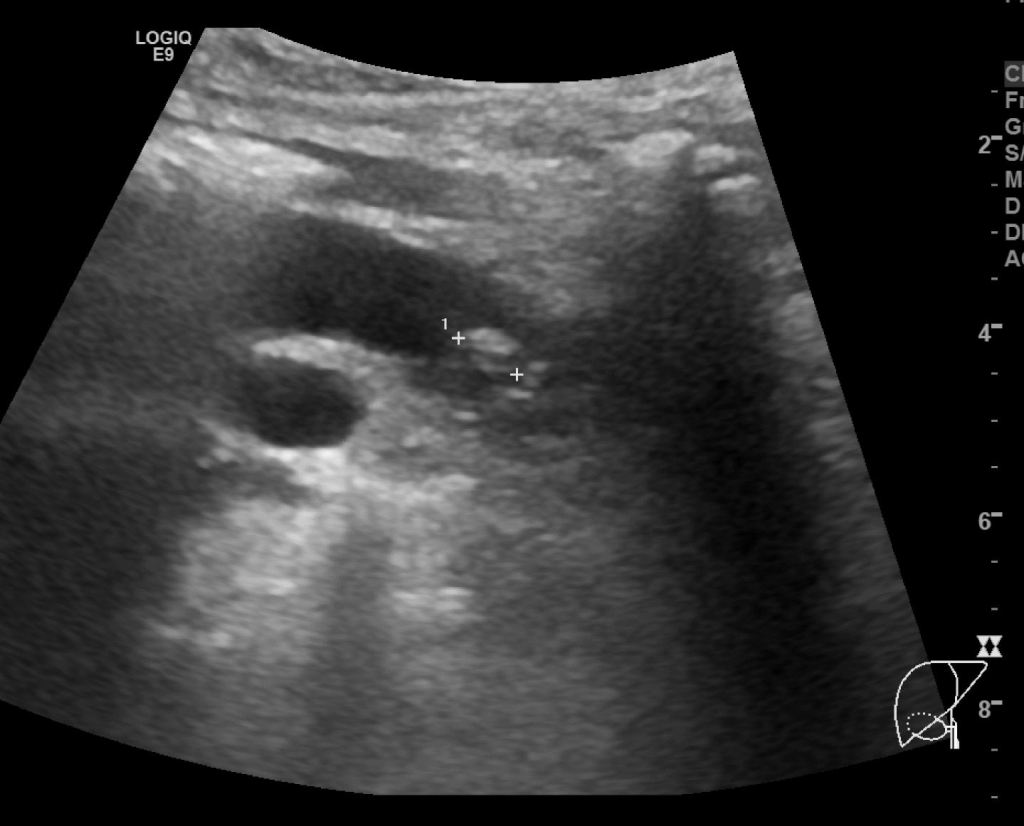

CT영상에서는 전혀 안보이던 총수담관 내 결석이 확인됩니다. 그리고, 결석 근처의 총수담관 벽이 불규칙하게 두꺼워져 보입니다.